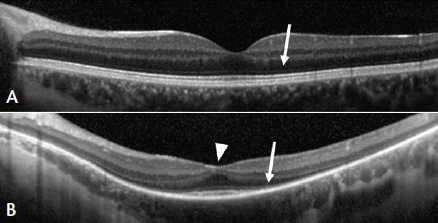

Figure 3. OCT scan through the fovea of a normal retina (A). The white arrow marks the outer nuclear layer where the photoreceptor nuclei are contained (A). OCT scan through the retina of a patient with XLRP (B) showing reduced contour of the foveal surface (white arrowhead) and diminished outer nuclear layer (white arrow).

More than 20 000 people in the United States and the European Union are estimated to have XLRP (Figure 3) and could potentially benefit from a gene therapy-based product.34 Although there are no approved treatments for any form of RP, studies have shown that certain nutritional supplements may slow disease progression. Some, including high-dose vitamin A palmitate for RP, remain controversial and associated with risk.35 Others, such as docosahexaenoic acid for XLRP, are under active investigation.36,37 For patients with RP who have little to no remaining vision, artificial vision devices such as the Argus II Retinal Prosthesis System (Second Sight Medical Products) have been shown to restore mobility vision.38 For patients in the vision-threatening stages of RP, however, gene therapy is an emerging potential option.